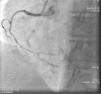

On admission the pain was decreasing; the physical examination was unremarkable, the electrocardiogram showed sinus rhythm, with negative T waves in the inferior leads, and troponin I was positive. The pain eventually disappeared after intravenous nitrates, and she was admitted to the coronary care unit. She underwent coronary angiography (Figure 1, Video 2), which revealed a spontaneous dissection of the posterior descending artery, with TIMI 2 flow, some posterolateral branches visualized from intercoronary collaterals, and severe vasospasm of the proximal right coronary artery (RCA), which reproduced the pain, relieved after intracoronary nitrates. No other unequivocal coronary lesions were noted, although a long dissection of the left anterior descending artery with intact intima cannot be excluded (Online Figure 2). It was decided not to perform percutaneous coronary intervention (PCI), and she was kept in the ward anticoagulated with subcutaneous enoxaparin (1 mg/kg twice daily), with dual antiplatelet therapy and a calcium channel blocker. Screening for autoimmune disease was negative. There were no events during hospitalization and she was scheduled for an angiographic review a week later, which showed progression of the dissection, with a wider false lumen (Figure 2, Video 3). Pain recurred during the procedure and a dissection was noted in a posterolateral branch. It was decided to perform PCI, and two bioabsorbable vascular scaffolds (BVS) were implanted in the PDA, guided by optical coherence tomography (OCT) coregistered with angiography. A third BVS was implanted in the distal RCA due to proximal progression of the dissection. A bare-metal stent was also implanted in the ostial RCA due to a traumatic dissection induced by the guiding catheter. Comparison of the images from angiography and OCT reveals a discrepancy in total (false plus true) diameter in the distal RCA (Figure 3, Video 4). After the procedure the patient was asymptomatic, although with a significant residual dissection in the RCA and posterolateral branch (Video 5). Anticoagulation was suspended and she was discharged five days later, with no further episodes of chest pain. Four months after this episode, she has had no recurrence of pain and is asymptomatic.

Distal right coronary artery (RCA) viewed by optical coherence tomography (OCT). Location of the OCT frame within the RCA is easily identified on the angiogram (arrow). Although the angiogram projection eventually captured the vessel at its smallest diameter (red line), this should be 4.03 mm as measured by OCT. By angiography the largest diameter of the segment is 2.1 mm. This suggests that the false lumen (F) is filled with a clear fluid, but not contrast, since on the angiogram only the true lumen (T) is visible, corresponding to the 2.07 mm mean true luminal diameter measured by OCT. Moreover, on OCT the catheter can be seen at the center of the vessel, but touching the intimal wall, while on the angiogram it appears adjacent to the wall, suggesting that only the true lumen is visible.

The discrepancy in lumen diameter during coregistration is an intriguing feature in this case, which could easily be attributed to technical inaccuracy. In fact, a blood-filled false lumen gradually being filled with contrast is the most likely explanation for this finding. However, unlike blood, which has high backscatter and variable attenuation, a uniform and completely black structure on OCT must represent a transparent fluid-filled structure, which is usually contrast. OCT in this case shows a very large total diameter vessel (4.19 mm in Figure 3) and suggests the false lumen was filled not with blood, but with a clear fluid which angiography indicated was not contrast, since it corresponds to a small diameter vessel (with contrast only in the true lumen – red arrow in Figure 3). Because a false lumen may require several contrast injections until it is completely opacified, especially if it is long and with a small entry point, comparison of OCT and angiography pictures taken after consecutive injections may be misleading, since the contrast content of the false lumen may be different. The coregistration applied in this case is essential in this regard, since it gives real-time coordinated comparison of the images. To our knowledge, a vessel wall effusion with clear fluid has never been reported in the pathophysiology of SCAD, so the explanation for this finding remains debatable, as it is difficult to interpret.